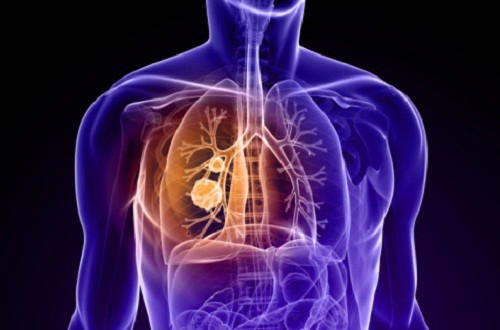

Il tumore al polmone è una categorizzazione sommaria di diversi tipi di tumore e cancro che possono interessare i polmoni. Fatto sta che non si tratta di una patologia semplice da curare, inoltre i polmoni stessi possono essere anche attaccati dalle metastasi di un cancro localizzato in altre zone del corpo. Le cause che possono essere in grado in aumentare in maniera significativa il rischio di contrarre una simile patologia sono oggigiorno molteplici. Rispetto ad alcuni decenni fa, il nostro stile di vita sembra essere maggiormente esposto alla contrazione di una simile malattia.

Di questi tempi infatti fra l’aria inquinata, il fumo, i prodotti di scarico e quelli chimici, le patologie che interessano i polmoni sono sempre più frequenti. E capire i sintomi per comprendere se si è davvero a rischio può salvarvi la vita. D’altro canto è risaputo che la prevenzione è sempre la migliore strategia da adottare specialmente nel caso di patologie molto gravi come quelle in oggetto. Ma quali sono i sintomi più frequenti del tumore al polmone?